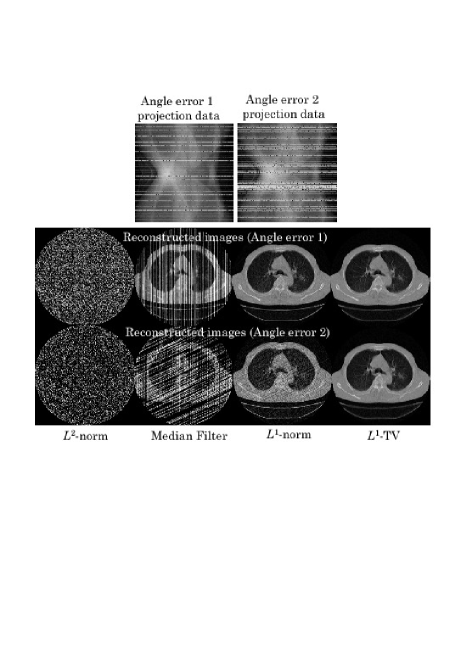

[Scenario 2](X-ray Radiation Errors) Two cases were simulated. In the first case, projection data bins corresponding to randomly selected angles (10 percent) were contaminated with the abnormal errors (Angle Error 1). In the second case, projection data bins corresponding to randomly selected angles (20 percent containing adjacent angles) were contaminated with the abnormal errors (Angle Error 2).

In all the scenarios, we used a single transaxial slice of chest CT scan image consisting of 320320 pixels. The simulated projection data was computed with the sampling of 320(angles)320(radial bins), from which an image consisting of 320320(pixels) was reconstructed. We have compared the following four different algorithms.

[-Norm Reconstruction] The -norm reconstruction of Eq. (22) was implemented with the iteration number 50.

[Projection Space Median Filter] This is an empirical method to remove the effect of abnormal errors. The median filter is applied to degraded projection data to remove the abnormal errors followed by the -norm reconstruction. The window size of median filter was empirically determined in such a way that visual quality of reconstructed image is best dependent on each case.

[-Norm Reconstruction] The -norm reconstruction (Algorithm 2) was implemented with the iteration number 50.

[-TV Reconstruction] The -TV reconstruction (Algorithm 3) was implemented with the iteration number 50.

We show reconstructed images together with the degraded projection data for all the scenarios in Figs. 3-5. In all the scenarios, the images by the -norm reconstruction were severely damaged by the abnormal errors, in which the artifact patterns, i.e. streaks, random errors, etc., depend on the locations of abnormal bins. The empirical projection space median filtering succeeded in reducing the artifacts, but the filtering also affects the correct data so that we can observe some additional artifacts in the final images. On the other hand, for the cases of Detector Error 1, Angle Error 1, and Random Error 1 with relatively mild errors, the power of identifying the abnormal bins in both the -norm and -TV reconstructions were significant in which they succeeded in reconstructing almost perfect images. However, the difference between the -norm reconstruction and the -TV reconstruction became apparent for the more difficult cases of Detector Error 2, Angle Error 2, and Random Error 2. In these cases, the -TV reconstruction correctly identified most of the abnormal bins whereas the -norm reconstruction did not succeed perfectly. With respect to convergence speed of the -norm and -TV reconstructions, they were a bit slower compared with the -norm reconstruction and the standard ART algorithm mainly because early iterations need to be spent to correctly identify the locations of abnormal bins. However, thanks to their row-action structures, they seem to be still significantly faster than using the standard -norm and -TV minimization algorithms (for example, popular iterative reweighted least-squares method [3],[4]) which can be used for the same cost functions.